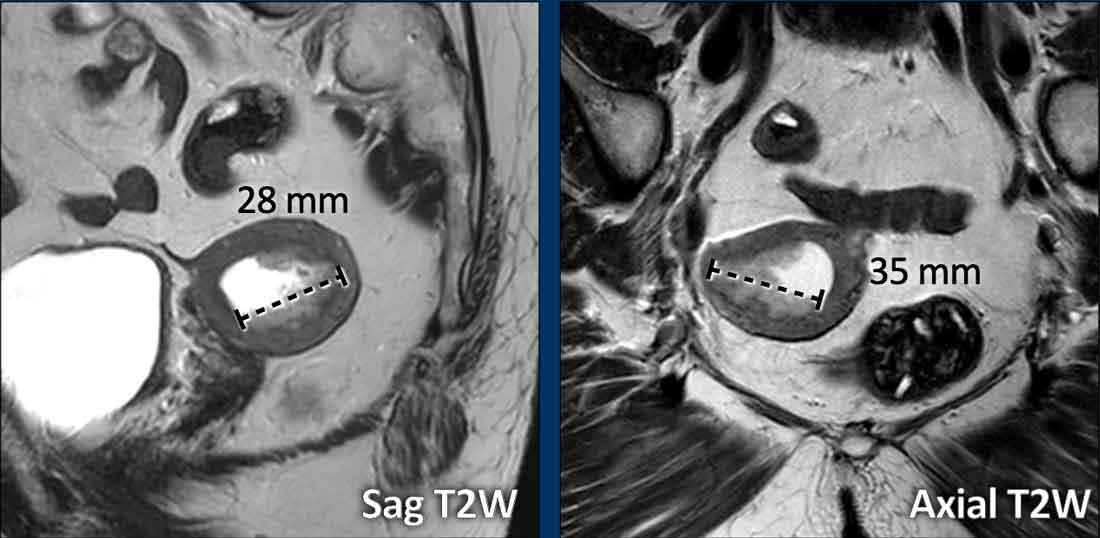

Trong các trường hợp dày lan tỏa hơn dọc theo lớp nội mạc tử cung, việc đo kích thước khối u có thể khó khăn hơn.

Hãy kiểm tra khối u trên nhiều mặt phẳng và tìm kích thước dài nhất có thể.

Trong trường hợp này, đường kính dài nhất của khối u được quan sát rõ nhất trên mặt phẳng ngang (axial) (hình).

Lưu ý rằng độ dày nội mạc tử cung bình thường thay đổi giữa phụ nữ tiền mãn kinh và hậu mãn kinh, với nhiều ngưỡng giá trị khác nhau được ghi nhận trong y văn:

- Tiền mãn kinh: ≤16 mm (độ dày thay đổi theo các giai đoạn khác nhau của chu kỳ kinh nguyệt)

- Hậu mãn kinh (thường 1-5 mm):

– Không có xuất huyết âm đạo: < 11 mm

– Có xuất huyết âm đạo và/hoặc đang dùng tamoxifen: < 5 mm

Các ngưỡng này được đề xuất để chỉ định đánh giá phụ khoa thêm.

Quyết định cuối cùng về các thăm dò tiếp theo cần luôn được thực hiện trên từng trường hợp cụ thể, có tính đến các triệu chứng lâm sàng, việc sử dụng tamoxifen và các yếu tố nguy cơ phát triển bệnh lý nội mạc tử cung.